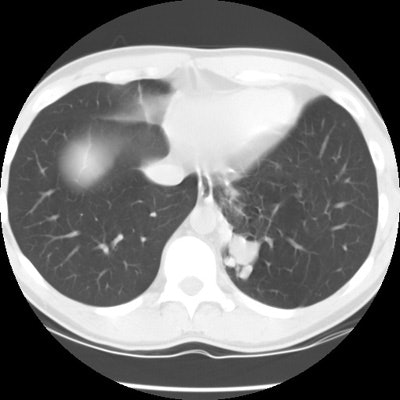

The patient below presented for evaluation of an abnormal CXR which demonstrated a left retrocardiac mass. (Click image to enlarge)

CT scan revealed a soft tissue mass in the left posterior-medial lung which had a branching tubular appearance. Some associated para-emphysematous changes were noted. (Click images to enlarge)